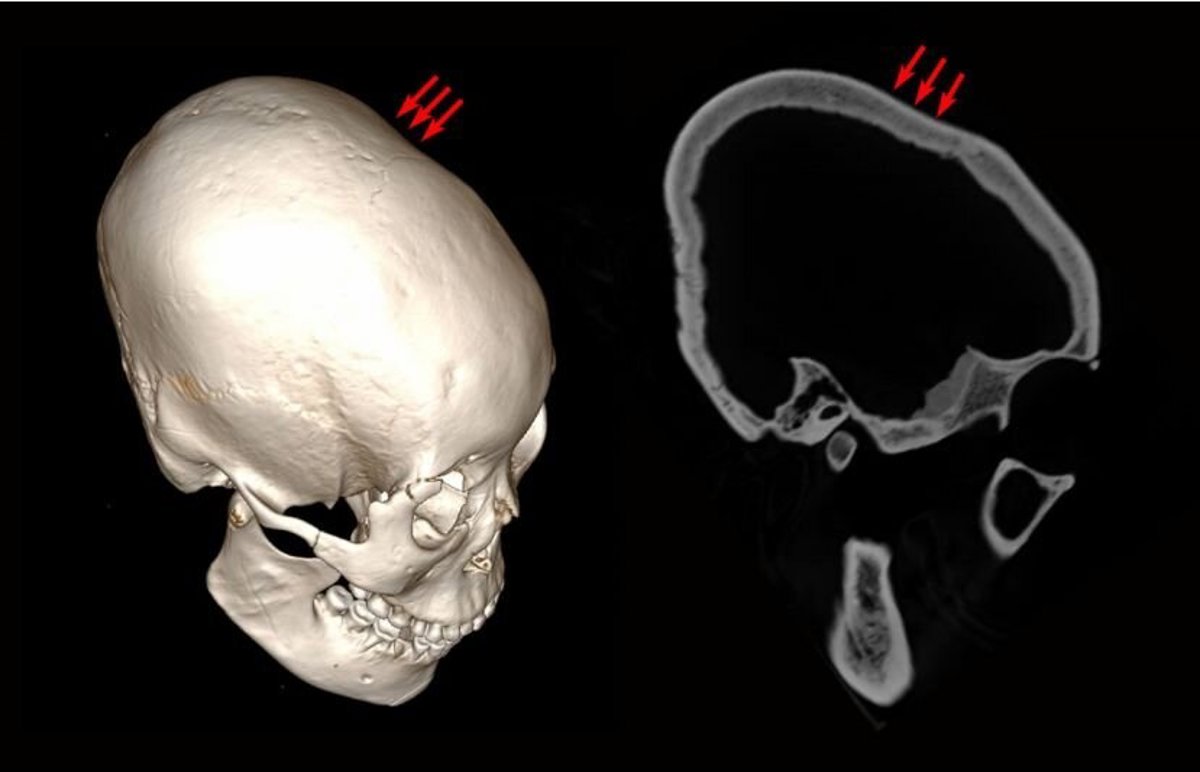

Algunos de los ejemplos más antiguos de alteración de las características físicas del cráneo en bebés han sido encontrados en un antiguo enterramiento al noreste de China.

Se encontraron veinticinco esqueletos en total, 11 de los cuales tenían evidencia de modificación craneal intencional. Cuatro de los cráneos eran de hombres adultos, uno era de una hembra adulta, y el resto eran de niños. Los huesos no se colocaron en la tumba al mismo tiempo, sin embargo, se enterraron a lo largo de 7.000 años, desde hace 12.000 a 5.000 años.